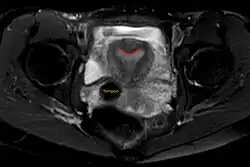

| Arcuate uterus (marked in red) seen on MRI | |

The arcuate uterus is a form of a uterine anomaly or variation where the uterine cavity displays a concave contour towards the fundus. Normally the uterine cavity is straight or convex towards the fundus on anterior-posterior imaging, but in the arcuate uterus the myometrium of the fundus dips into the cavity and may form a small septation. The distinction between an arcuate uterus and a septate uterus is not standardized.

A transvaginal ultrasound can reveal the condition.

Helpful techniques to investigate the uterine structure are transvaginal ultrasonography and sonohysterography, hysterosalpingography, MRI, and hysteroscopy. More recently 3-D ultrasonography has been advocated as an excellent non-invasive method to delineate the condition.[5]